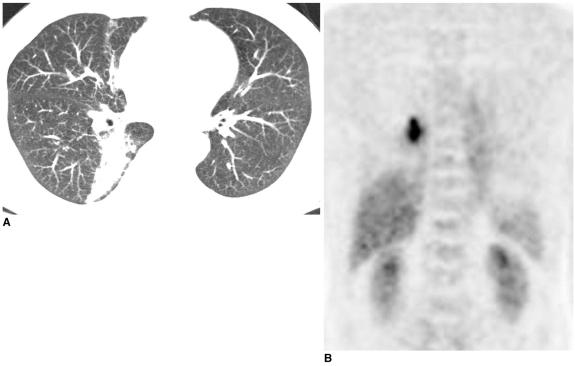

Fluorodeoxyglucose (FDG)-positron emission tomography (PET) is being used more and more to differentiate benign from malignant focal lesions and it has been shown to be more efficacious than conventional chest computed tomography (CT). However, FDG is not a cancer-specific agent, and false positive findings in benign diseases have been reported. Infectious diseases (mycobacterial, fungal, bacterial infection), sarcoidosis, radiation pneumonitis and post-operative surgical conditions have shown intense uptake on PET scan. On the other hand, tumors with low glycolytic activity such as adenomas, bronchioloalveolar carcinomas, carcinoid tumors, low grade lymphomas and small sized tumors have revealed false negative findings on PET scan. Furthermore, in diseases located near the physiologic uptake sites (heart, bladder, kidney, and liver), FDG-PET should be complemented with other imaging modalities to confirm results and to minimize false negative findings. Familiarity with these false positive and negative findings will help radiologists interpret PET scans more accurately and also will help to determine the significance of the findings. In this review, we illustrate false positive and negative findings of PET scan in a variety of diseases.